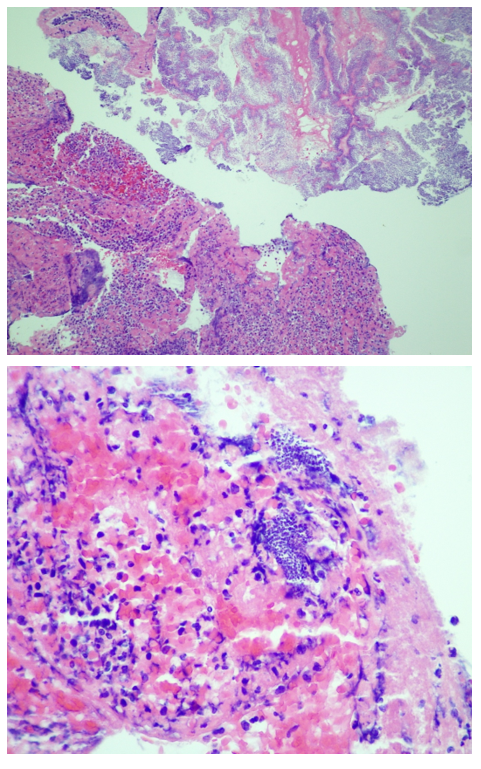

The Gram stain of the driveline exit site was unremarkable, with no organisms and few neutrophils seen. Aerobic cultures yielded a light amount of gram positive cocci in addition to mixed skin flora. Colonies were small, and weakly beta hemolytic on blood agar (Image 1A). This organism was catalase- and coagulase-positive, and definitively identified as Staphylococcus aureus by MALDI-TOF MS. Susceptibility testing was performed by broth microdilution, where the organism was determined to be a vancomycin-intermediate Staphylococcus aureus (VISA, MIC=4, Image 1C). Due to the unusual nature of the result, it repeated and confirmed by E-test (Image IB) in our laboratory, and independently verified at our contract reference laboratory. The isolate was also referred to the Texas State Public Health Laboratory where the vancomycin-intermediate phenotype was again confirmed. This isolate was also daptomycin non-susceptible, but remained susceptible to oxacillin, trimethoprim/sulfamethoxazole, linezolid, rifampin, and clindamycin.